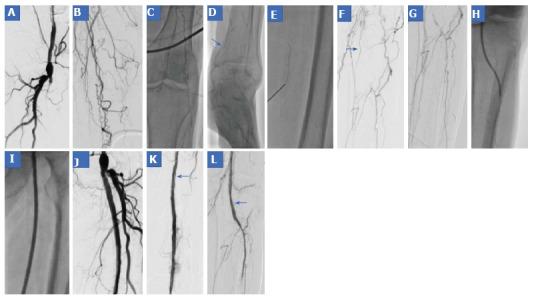

Patients with critical limb ischemia necessitate immediate intervention to restore blood flow to the affected limb. Endovascular procedures are currently preferred for these patients. We describe the case of an 80-year-old female patient who presented to our department with ischemic rest pain and ulceration of the left limb. The patient had history of left femoral popliteal bypass surgery, femoral thromboendarterectomy and patch angioplasty of the same limb 2 years ago. Doppler sonography and magnetic resonance angiography revealed an occlusion of the left superficial femoral artery (SFA) and popliteal artery and of all three infra-popliteal arteries. Due to severe comorbidities, the patient was scheduled for a digital subtraction angiography. An antegrade approach was first attempted, however the occlusion could not be passed. After revision of the angiography acquisition, a stent was identified at the level of the mid SFA, which was subsequently directly punctured, facilitating the retrograde crossing of the occlusion. Thereafter, balloon angioplasty was performed in the SFA, popliteal artery and posterior tibial artery. The result was considered suboptimal, but due to the large amount of contrast agent used, a second angiography was planned in 4 wk. In the second session, drug coated balloons were used to optimize treatment of the SFA, combined with recanalization of the left fibular artery, to optimize outflow. The post-procedural course was uneventful. Ischemic pain resolved completely after the procedure and at 8 wk of follow-up and the foot ulceration completely healed.

严重肢体缺血患者需要立即进行干预以恢复患肢的血流。目前,血管内介入手术是这类患者的首选治疗方法。我们描述了一名80岁女性患者的病例,该患者因左下肢缺血性静息痛和溃疡前来我院就诊。患者2年前曾接受左股腘动脉搭桥手术、股动脉血栓内膜切除术及同肢体的补片血管成形术。多普勒超声和磁共振血管造影显示左股浅动脉(SFA)、腘动脉以及所有三支腘下动脉均闭塞。由于存在严重的合并症,该患者计划接受数字减影血管造影检查。首先尝试顺行入路,但闭塞部位无法通过。在重新评估血管造影图像后,发现在SFA中段水平有一枚支架,随后直接对其进行穿刺,从而实现了闭塞部位的逆行通过。此后,对SFA、腘动脉和胫后动脉进行了球囊血管成形术。结果被认为不太理想,但由于使用了大量造影剂,计划在4周后进行第二次血管造影。在第二次手术中,使用药物涂层球囊对SFA进行优化治疗,并对左腓动脉进行再通以优化流出道。术后过程顺利。术后缺血性疼痛完全缓解,随访8周时足部溃疡完全愈合。